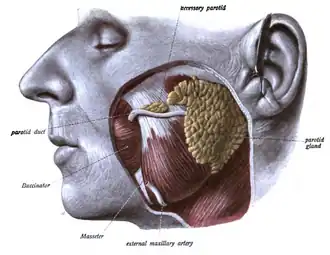

Chez l'homme, le conduit parotidien est un conduit à parois épaisses, légèrement aplati, mesurant 4 à 7 cm de long, et 3 mm de diamètre. Il naît de la glande, dans l'épaisseur de la parotide, par l’union de deux racines le plus souvent, avant d'émerger de son bord antérieur. Il passe sur le bord externe du muscle masticateur ou masséter, dans un dédoublement du fascia masséterique, puis par la région génienne en passant devant le corps adipeux de la joue (boule de Bichat) avant de traverser enfin le muscle buccinateur.

Schéma anatomique représentant le trajet du canal parotidien

- Dissection anatomique représentant le trajet du conduit parotidien de la glande parotidienne à son coude